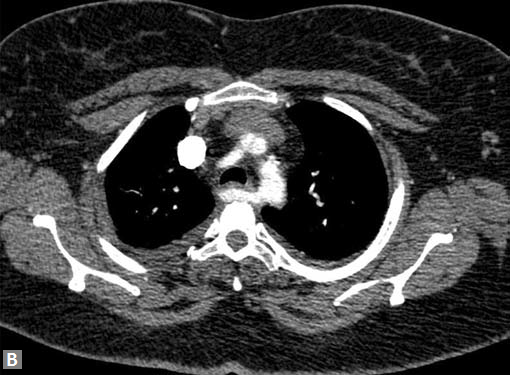

On occasions, thromboembolism can also be seen in right

ventricle and less commonly in pulmonary veins. Systemic

vein thrombus (innominate veins, SVC, IVC) sometimes

accompanies pulmonary thromboembolism (Figs 18A and B).